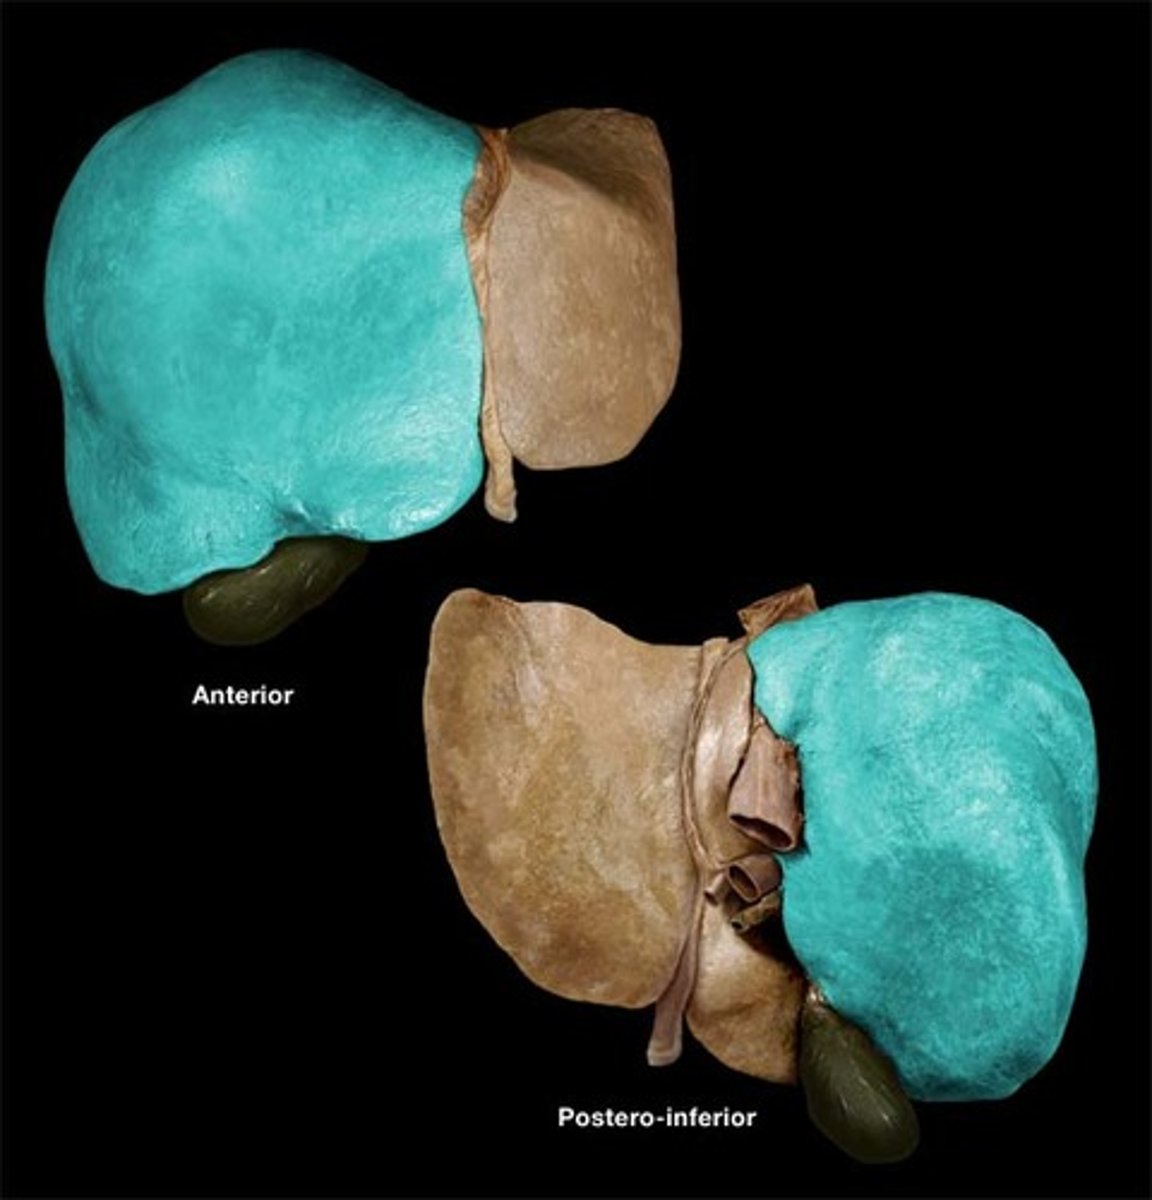

diaphragmatic surface (of spleen)

spleen

produces, stores, and eliminates blood cells

visceral surface (of spleen)

hilum (of spleen)

splenic vein